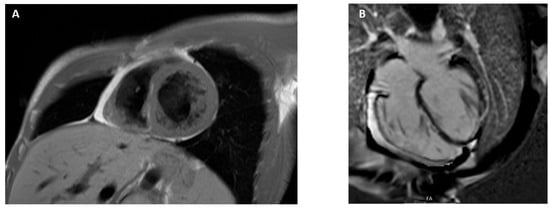

3.9. Arrhythmogenic Cardiomyopathy

4. CMR Applications in Ischemic Heart Disease